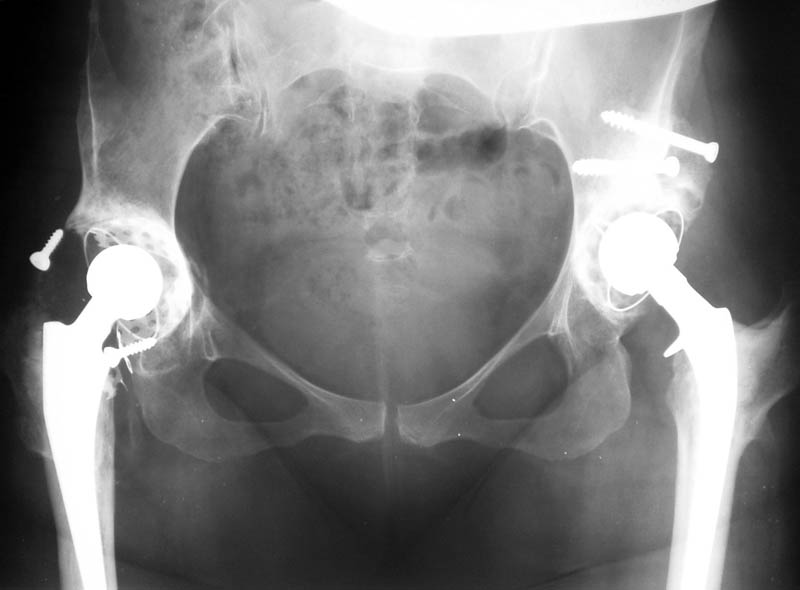

Мужчина, 38 лет. Двусторонний диспластический коксартрз, кифосколиоз.Правый сустав прооперирован 12.12.00, левый - в апреле 2003 г. Справа вывихнулась <чашка>.

Предполагается заменить <чашку>, наростив крышу <тутопластом>? Возможно ли использовать бесцементную <чашку>? Мнения? Заранее благодарю! С уважением,А.В.Владзимирский